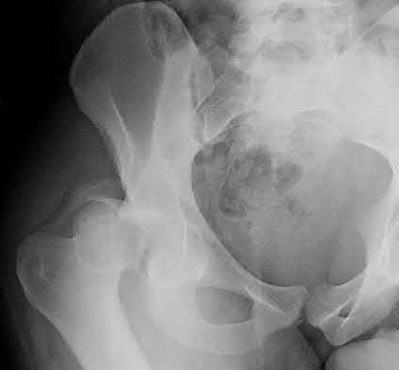

Question 12:

A 55-year-old patient presents with a slowly enlarging, painful mass in the proximal humerus. Biopsy reveals a hyaline cartilage matrix with cellular atypia, confirming a diagnosis of central conventional chondrosarcoma. Which of the following genetic mutations is most frequently identified in this specific tumor?

Correct Answer: IDH1 / IDH2

Explanation:

Mutations in the isocitrate dehydrogenase genes, IDH1 and IDH2, are found in up to 50-60% of central conventional chondrosarcomas and enchondromas. EXT1 and EXT2 mutations are characteristic of multiple hereditary exostoses (osteochondromas). GNAS mutations are seen in fibrous dysplasia. TP53 and RB1 mutations are hallmark aberrations in osteosarcoma.